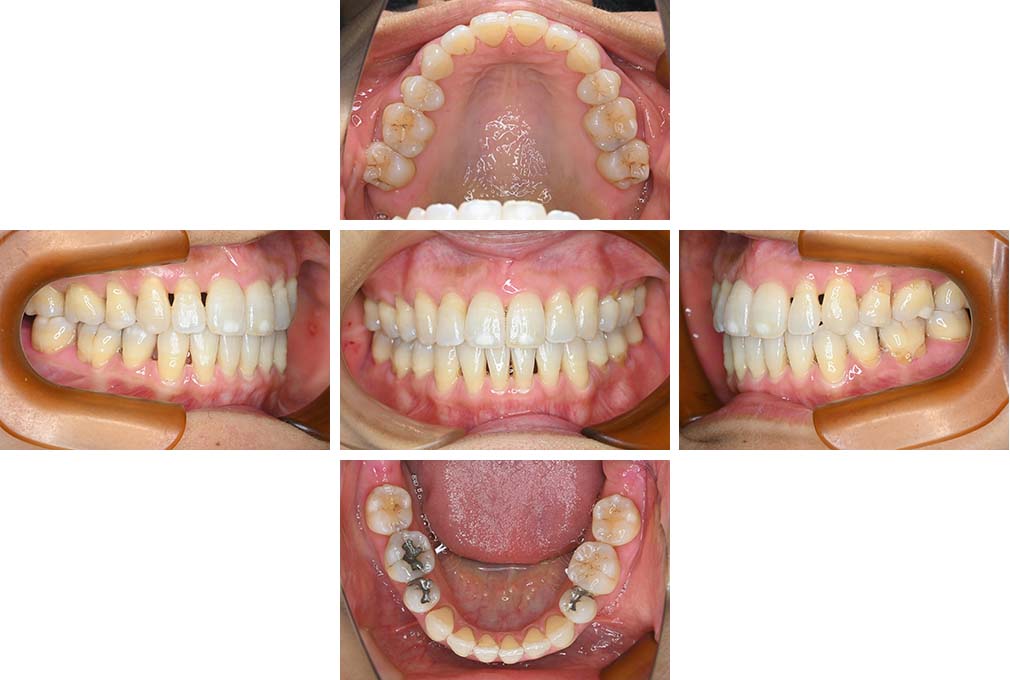

CASE:02

下顎前歯部叢生、小臼歯4歯先天欠損

初診時年齢 14歳3か月

性別 女性

治療費の目安 70万円(治療開始時)

上顎左右側小臼歯3歯、下顎左側第二小臼歯の先天欠損と下顎前歯の叢生を主訴として近隣一般歯科から紹介来院した。

上顎左側第一、第二小臼歯、右側第一小臼歯、下顎左側第二小臼歯が先天欠損であったが、左上第二乳臼歯の根の吸収がほぼ無いことから、これを残すこととして、下顎左側乳臼歯と、右側第二小臼歯を抜歯していただきマルチブラケット装置を使用して動的治療を行った。矯正用ゴムなどの協力状態も良く2年0カ月(調整来院19回)で装置を撤去し保定へ移行した。動的治療終了13年2カ月での来院時には下顎左右側智歯が萌出していたが、垂直的に萌出していたため抜歯は行っていない。

治療前

14歳3か月

治療後

動的治療期間2年0カ月

16歳7か月

13年経過

動的治療終了後13年2カ月

30歳0か月